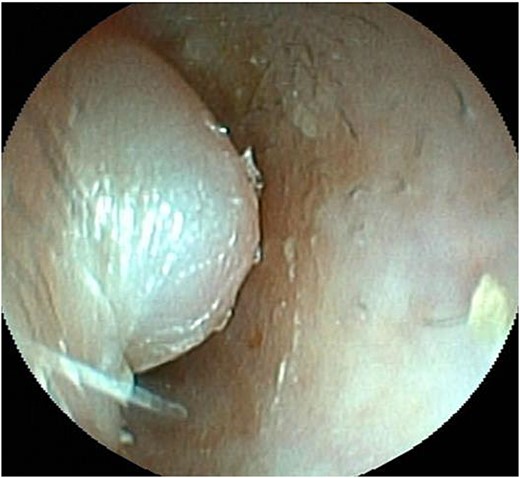

A 62-year-old man presented with a left external auditory canal obstruction and a smooth swelling on the anterior wall. Audiological exams showed no abnormalities, and no otorrhea was observed. Medical history included emphysema, duodenal cancer, and gastric ulcer. The patient was diagnosed with an external auditory canal cyst and underwent cystectomy at the Department of Otorhinolaryngology of our hospital in February 2017. Histopathological examination revealed a cystic lesion without epithelial lining, diagnosed as a ganglion-like lesion. In May of the same year, the swelling was observed again (Fig. 1). The patient was referred to our department for further investigation because computed tomography (CT) revealed enlargement of the left mandibular head (Fig. 2). Clinical findings at the time of consultation included symmetrical facial appearance and a maximum range of motion of 55 mm in the mandible. Upon opening the mouth, crepitus was observed in the left TMJ; however, no restriction of the lateral or anterior movement of the mandible or occlusal deviation was observed. There was no pain in opening the mouth or tenderness in the TMJ. The anterior wall of the left external auditory canal was swollen, with elasticity and no mobility. T2-weighted magnetic resonance imaging revealed an internal high-signal mass in the external auditory canal (Fig. 3).

Endoscopic view of the auditory canal. Swelling of the anterior wall of the left lateral auditory canal.